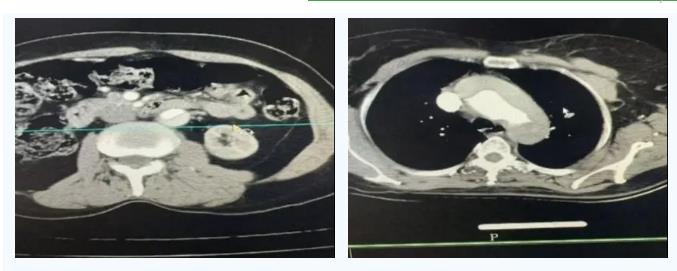

2025年7月,马文娟告别家乡与熟悉的工作岗位,跨越千里来到玉树州称多县人民医院,肩负起青海红十字医院赋予的重任——以支医队员身份来到称多县人民医院工作,让高原群众在家门口享受到优质的放射诊疗服务。8月26日,帮扶队长师红彪紧急通知,玉树州人民医院急需CT增强扫描技术人员支援,作为青海红十字医院派出的骨干技师,马文娟在接到通知的第一时间便启程赶往州医院,开启为期一周的紧急帮扶工作。她清晰记得第一次走进州医院影像科的情景:崭新的CT设备与匮乏的专业人才形成鲜明对比,“设备有了,但没人能充分发挥它的价值,这就像有了最好的望远镜却不知道如何对准星空,而我们的使命,就是帮大家学会‘瞄准’疾病。”

接下来的一周,马文娟以青海红十字医院放射科的标准化诊疗流程为基础,紧急制定出针对性CT增强扫描计划,与玉树州放射科主任反复沟通,结合当地常见病、多发病特点设计专业培训内容——从基础操作规范到头颅灌注、肺动脉CTA、主动脉CTA等复杂扫描技术,手把手带教科室技术人员;她还联合科主任开展《造影剂的临床应用》专题讲座,结合青海红十字医院的临床案例,让当地临床医生精准掌握CT增强扫描的适应证与禁忌证,确保患者能在第一时间得到合适的检查。州医院放射科医生江巴感慨地说:“马老师不仅把青海红十字医院的专业技术教给我们,还教我们如何像红十字医生那样,用耐心沟通结合临床病史做出更准确的判断。”

在玉树州医院一周的帮扶时间虽短,但成效显著:玉树州医院放射科技师已能独立完成常见病的CT扫描和诊断;马文娟还将青海红十字医院的标准化扫描方案与当地实际结合,整理成《针对性CT扫描方案手册》,留给州医院放射科同仁,供大家随时学习巩固。

CT扫描的黑白影像里,映射着生命的脆弱与坚韧;而马文娟的帮扶故事,更诠释了青海红十字医院在青南支医帮扶工作中的深远意义——它从未局限于技术与设备的简单转移,而是以“红十字”为纽带,将优质医疗资源下沉到高原最需要的地方,让“大病不出州”从愿景变为现实;它不仅是医疗能力的提升,更是生命与生命的温暖联结,是红十字精神在高原上的生动实践,让每一位高原群众都能感受到医疗帮扶带来的希望与温暖。